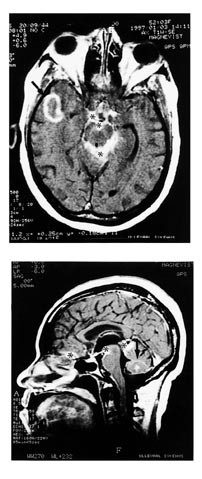

CT og MR viste ringoppladende lesjoner i hjernevevet og markert kontrastoppladning av subaraknoidalrom og hjernehinner i basale cisterner. Bildet ble tolket som sannsynlig cerebral tuberkulose. Dyrking av cerebrospinalvæske var imidlertid negativ på syrefaste staver, men umiddelbart før hun døde, kom det oppvekst av sopp. Åpen hjernebiopsi tatt tre dager før døden viste granulomatøs betennelse med soppelementer.

Pasienten. En 51 år gammel kvinne som ikke hadde besøkt Latin-Amerika fra hun innvandret til Norge fra Brasil 23 år tidligere, var sommeren 1995 innlagt i et annet sykehus i forbindelse med forbigående svimmelhet og kvalme. Høsten 1996 fikk hun i løpet av en uke hodepine, kvalme og pareser i venstre arm og bein med falltendens mot venstre. Hun fikk også nedsatt hørsel og smerter bak høyre øre. Hun ble innlagt i vårt sykehus i begynnelsen av oktober 1996. MR-undersøkelse viste kontrastoppladning i subaraknoidalrom og hjernehinnene på skallebasis og rundt hjernestammen. I tillegg var det to ringoppladende lesjoner i høyre tinninglapp og i vermisregionen i lillehjernen (fig 1a, b). Ny gransking av CT-bilder viste at vermislesjonen var til stede ved innleggelsen i 1995. Spinalvæsken inneholdt 124 celler/mm 3 (overveiende granulocytter), spinalprotein var forhøyet (2 100 mg/l) og spinalglukose var nedsatt (1,6 mM/l). Det var ikke oppvekst av bakterier i kulturer fra cerebrospinalvæske tatt ved innkomst. Det var ingen serologiske holdepunkter for HIV-infeksjon, toksoplasmose, syfilis eller borreliose. PCR-undersøkelse av serum gav ingen holdepunkter for infeksjon med varicella zoster-virus eller herpes simplexvirus. Lungerøntgen og CT abdomen var negative, hemoglobinnivået var 12,4 g/100 ml, SR 15 mm, CRP 5 mg/l. Det ble ansett som mest sannsynlig at sykdomsbildet representerte tuberkuløs meningitt med lokaliserte tuberkulomer i storhjerne og lillehjerne. Man vurderte hjernebiopsi, men dette ble ikke utført. Hun fikk antituberkuløs behandling med Zinamid 500 mg ⋅ 3, Rimactan 600 mg

⋅ 1, Isoniazid 300 mg ⋅ 1 og Pyridoxin 40 mg ⋅ 1. Det kom tegn på forhøyet hjernetrykk, og hun fikk derfor Prednisolon 30 – 40 mg/døgn. Hun ble etter hvert subfebril. Etter seks ukers behandling utviklet hun tonisk-kloniske krampeanfall og ble reinnlagt. I de neste ukene tilkom ptose, urininkontinens og varierende grad av facialisparese. Fra spinalvæskeprøvene ble det rekvirert dyrking med hensyn på mykobakterier, men ikke på sopp. Etter til sammen 11 ukers dyrking i vekstmedium for mykobakterier ble det 6.1. 1997 funnet organismer som dannet gjærcelleliknende kolonier. Samme dag ble pasienten funnet komatøs. På vital indikasjon ble det 7.1. 1997 tatt biopsi fra lesjonen i høyre tinninglapp. Etter operasjonen var hun dypt komatøs og hadde lysstive pupiller. Hun døde tre dager senere. Obduksjon ble nektet.